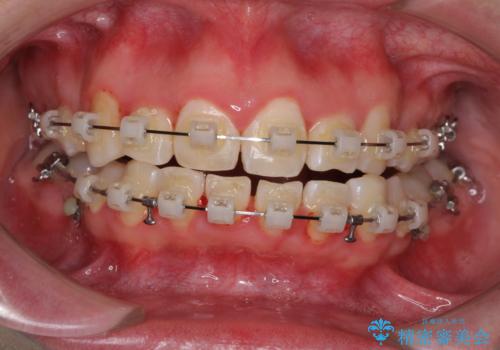

治療中に舌の突出癖が改善されず、下顎前歯が著しく前方に突出して反対咬合となってしまう局面がありました。

アンカースクリューを使用しながら舌癖の改善を図り、何とか咬み合わせを改善することができました。